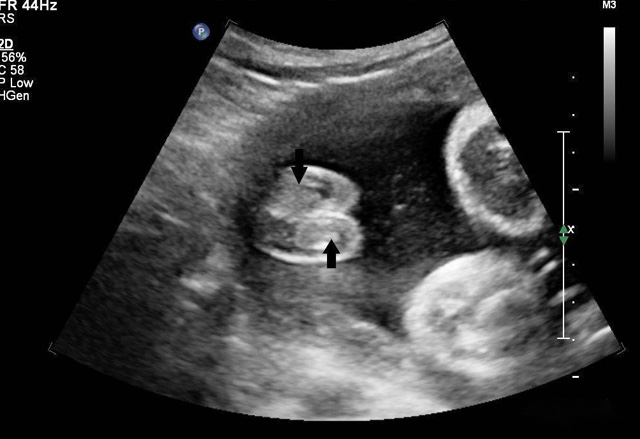

動(dòng)態(tài)三維超聲成像有時(shí)間因素(心動(dòng)周期)三維超聲成像分為靜態(tài)三維超聲成像和動(dòng)態(tài)三維超聲成像,整體成像法重建感區(qū)域?qū)崟r(shí)活動(dòng)的三維圖像,稱為四維超聲心動(dòng)。

三維超聲技術(shù)可用于心臟、腹腔、婦科、產(chǎn)科、小器官、血栓、血管成像等多方面。